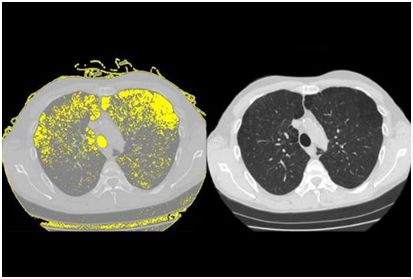

高达 30%的接受抗逆转录病毒疗法治疗的艾滋病毒患者发展为慢性肺病肺气肿。 Weill Cornell 医学研究人员的新研究发现了一种可能解释为什么会发生肺损伤的机制。

研究人员在“细胞报告”5 月 9 日发表的研究报告中显示,人类免疫缺陷病毒或 HIV 与干细胞结合,称为基底细胞,其转化为其他类型的细胞。该过程重新编程基底细胞,导致它们释放被称为蛋白酶的酶,其可以破坏肺组织并在进行氧气交换的空气囊的壁中戳出孔。

为了进行这项研究,调查人员将正常的人气道基底细胞从健康非吸烟者的肺部收集,并在观察下暴露于艾滋病毒一段时间。将病毒与基底细胞表面结合并重新编程,以开始产生可以分解蛋白质并破坏组织的酶或蛋白酶,称为金属蛋白酶 -9。因为研究人员知道肺气肿是气道疾病,这一发现表明,当基底细胞呈现称为“破坏性表型”的晶型时,他们开始在健康组织中消失,这会及时得导致肺气肿。